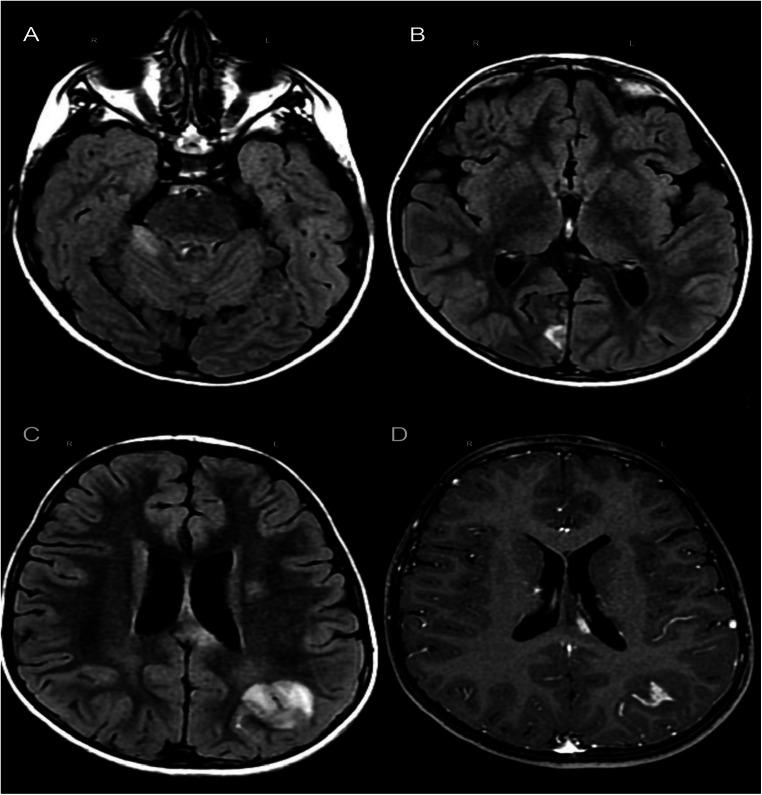

We present a case regarding a 6-year-old patient suffering from Fisher-Evans syndrome who was given sirolimus and thalidomide therapy. After 10 days since the first positive nasopharyngeal swab for Sars-CoV-2, in which he had no symptoms, he presented an episode of generalized tonic-clonic seizure with spontaneous resolution. The patient underwent MRI which showed the typical picture of acute disseminated encephalomyelitis. His clinical course was favorable, with a good response to cortisone therapy and a progressive improvement of the neuroradiological and electroencephalographic picture.

我们报告了一例 6 岁 Fisher-Evans 综合征患儿的病例,他接受了西罗莫司和沙利度胺治疗。在首次鼻咽拭子检测出 Sars-CoV-2 阳性(无任何症状)后的 10 天,他出现了全面性强直阵挛性发作,自行缓解。患者接受了 MRI 检查,显示出急性播散性脑脊髓炎的典型表现。他的临床病程良好,对皮质激素治疗反应良好,神经影像学和脑电图表现逐渐改善。